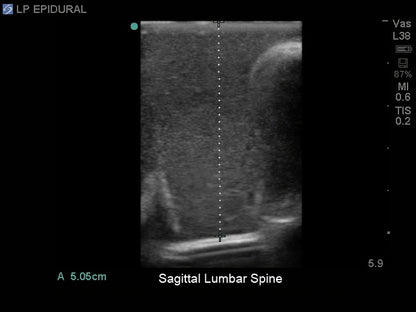

The lumbar puncture and lumbar epidural tissue insert is constructed using Blue Phantom self-healing and ultra-durable tissue. Our durability provides you with better training at a better cost. Our patented tissue is superb in ultrasound imaging characteristics and provides the same tactile feedback as real human tissue. With your Blue Phantom training model and the ultrasound system of your choice, you can expect the same level of quality experienced imaging patients in a clinical environment. Blue Phantom lumbar puncture and lumbar epidural replacement insert will perform optimally using any ultrasound imaging system configured with the appropriate ultrasound transducer.

- Ultrasound can be used for identification of the optimal insertion points, angle of needle insertion, and determination of the depth to the ligamentum flavum, epidural space, and spinal cistern